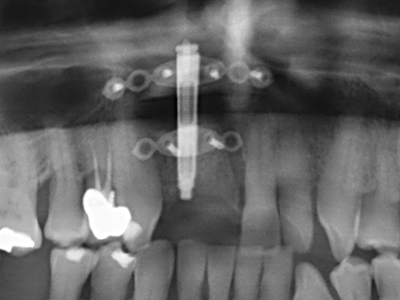

Wie sich in der Vergangenheit gezeigt hat stellt prinzipiell jeder knochenchirurgische Eingriff eine mögliche Indikation für die Piezochirurgie dar. So lässt sich die Präparation des mobilen Segmentes bei der Distraktionsosteogenese (Abb. 23-25) und der Sandwichosteotomie mit speziellen Ansätzen bewerkstelligen, ohne die für den Erfolg beider Techniken essenzielle Blutversorgung des krestalen Anteils zu gefährden (Gonzalez-Garcia, Diniz-Freitas et al. 2008).

Für die Entnahme von Implantaten ist die Präparation eines vestibulären Knochendeckels möglich, der nach Entfernung der Implantatschraube refixiert wird und auf diesem Wege die Kontur des Alveolarfortsatzes erhält.

Weitere Einsatzgebiete ergeben sich in der Kieferhöhlenchirurgie: Hier können nach konzentrischer Präparation eines in der Regel trapezförmigen Knochendeckels der fazialen Kieferhöhlenwand Pathologien und Fremdkörper aus der Kieferhöhle entfernt werden. Der Knochendeckel wird nach Abschluss des intra-antralen Operationsanteils reponiert und durch Verkeilen oder adaptierende Nähte gegen Dislokation gesichert.